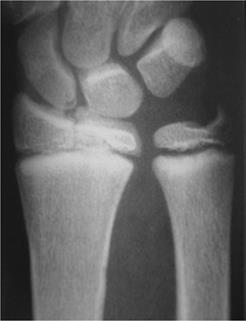

Imaging

• Radiographs

• recommended views

• AP and lateral of wrist

• AP and lateral of forearm

• AP and lateral of elbow if tender about elbow, or diaphyseal fractures present

• findings

• in addition to fracture must evaluate for associated injuries

• scapholunate interval

• DRUJ (distal radio-ulnar joint)

• ulnar styloid

• elbow injuries